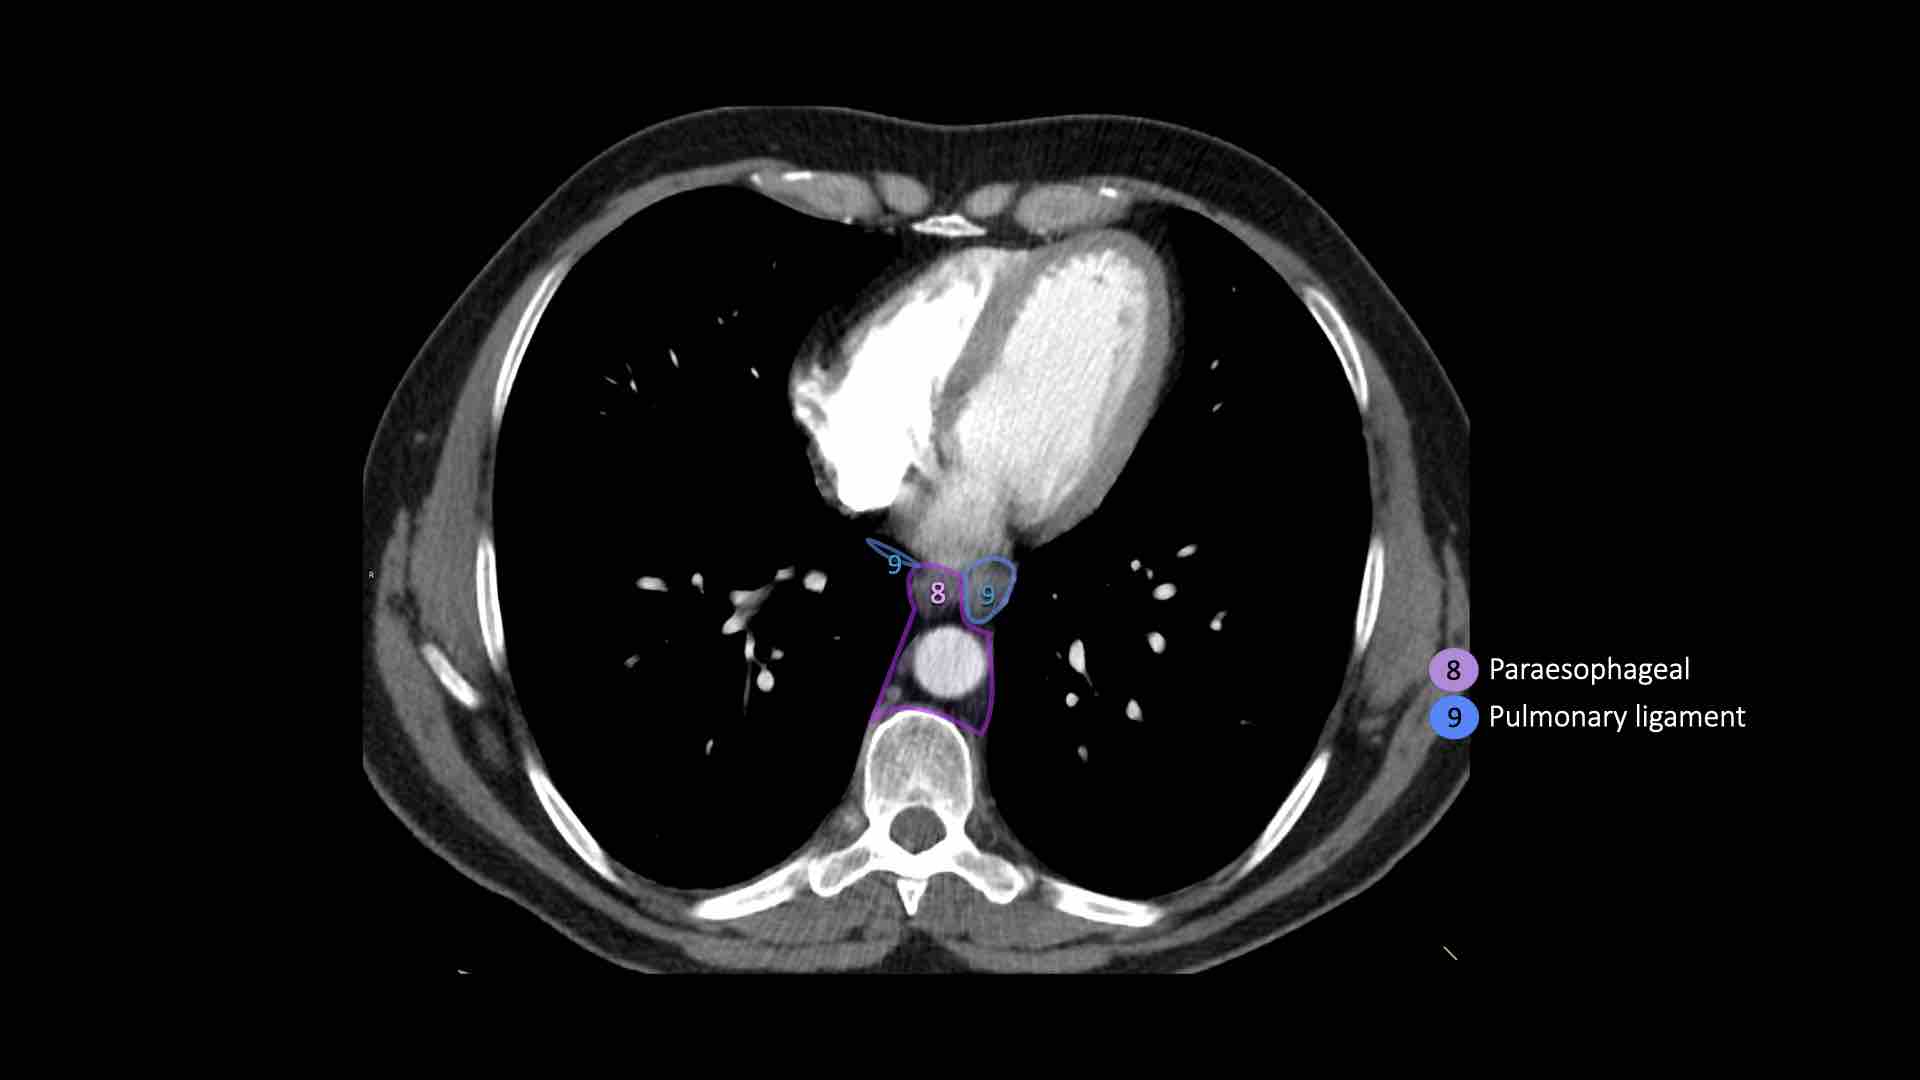

8. Cạnh thực quản

Các hạch nằm dưới carina.

9. Dây chằng phổi

Các hạch nằm trong dây chằng phổi.

8. Hạch cạnh thực quản

Các hạch này nằm bên dưới các hạch dưới carina và trải dài xuống đến cơ hoành.

Bên trái là hình ảnh dưới mức carina.

Bên phải thực quản là một hạch nhóm 8.

9. Hạch dây chằng phổi

Hạch dây chằng phổi nằm trong dây chằng phổi, bao gồm các hạch ở thành sau và phần dưới của tĩnh mạch phổi dưới.

Dây chằng phổi là phần kéo dài xuống dưới của các nếp gấp màng phổi trung thất bao quanh rốn phổi.